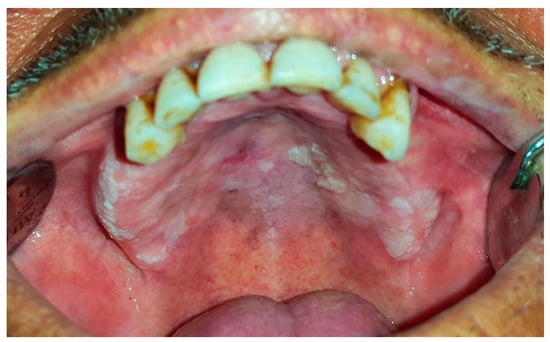

6.7. Nicotinic Stomatitis

| Nicotinic stomatitis | >45 | M | palate | diffuse leathery grayish-white palatal plaque with red points, “dried mud” appearance | regression after cessation of smoking | not a premalignant condition |